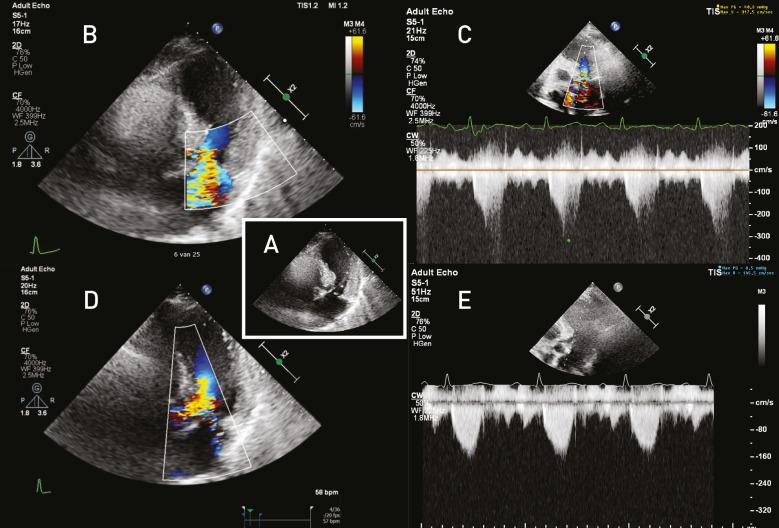

We report a case of a 73-year-old female patient, who was admitted to the coronary care unit due to chest pain, malaise and near syncope. During physical examination, the patient was hypotensive and there were signs of left-sided heart failure and a loud systolic murmur. Echocardiogram showed apical ballooning with dynamic left ventricular outflow tract obstruction, based on systolic anterior motion of the mitral valve with important mitral valve regurgitation. In the acute setting, the cardiogenic shock was treated cautiously with fluid resuscitation and intravenous metoprolol, resulting in direct stabilisation of her haemodynamic condition. As a codiagnosis, there was a significant stenosis of left anterior descending artery, which was treated successfully by percutaneous coronary intervention with drug eluting stents. During follow-up, left ventricular function normalised, and the left ventricular outflow tract obstruction, systolic anterior motion of mitral valve and related mitral regurgitation all resolved.

摘要